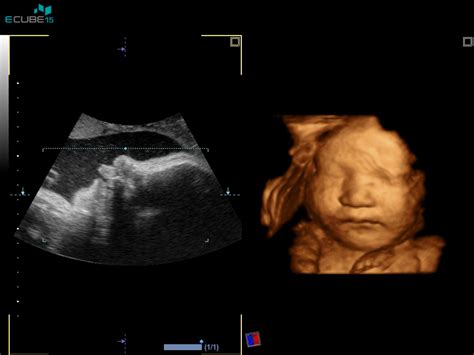

V primeru, da so vam na UZ kontroli rasti ugotovili, da je otroček manjši in droben, čeprav ste noseči 33 tednov in 4 dni, vse mere pa ustrezajo 31 tednom in 4 dnem, je pomembno, da se ne prehitro prestrašite. Če otrok raste skoraj vzporedno s spodnjo mejo že od polovice nosečnosti, zdravnik običajno svetuje, da ne bi smel biti mlajši, ampak samo manjši in bolj droben. To je še posebej verjetno, če sta oba s partnerjem manjše rasti. V takem primeru je priporočljivo še enkrat opraviti pregled v 37. tednu, da se zagotovi, da otrok ne pade pod spodnjo mejo rasti, vendar za zdaj ni razloga za paniko.

Pomembno je vedeti, da pri ultrazvočnih meritvah obstaja odstopanje +/- 10%. Če sta oba starša manjše postave, je povsem normalno, da bo tudi vajin otrok manjši in bolj droben. Povprečne vrednosti v tabelah so pogosto zgolj orientacijske. Velikost trebuha je bolj odvisna od tega, kje nosite otroka (spredaj ali zadaj), kot od dejanske velikosti otroka. Če sta vi in vaš partner manjše rasti, otrok naravnost ne more biti velikan.

Nekateri strokovnjaki menijo, da se meritve z ultrazvokom po 20. tednu nosečnosti lahko izkažejo za precej zavajajoče zaradi velikih odstopanj. Zato je ključnega pomena zaupati svojemu zdravniku. Če pa mu ne zaupate, je dobro poiskati drugo mnenje.

Zgodbe o Natančnosti Ultrazvočnih Meritev

Obstajajo številne izkušnje, ki kažejo, da ultrazvočne napovedi glede velikosti in teže otroka niso vedno natančne. Nekaterim so napovedali drobnega otročička, celo teden pred rojstvom so opozarjali, da bo teža okoli 3 kg, vendar se je rodila deklica s 3790g. V drugem primeru so svakinji napovedovali "drobižka", ki bo majhen fantek, a se je rodil s 4280g. Te izkušnje kažejo, da se ljudje pogosto vznemirjajo zaradi napačnih napovedi, saj meritve niso vedno zanesljive. Tudi v primeru prezgodnjega poroda, ko so sporočili zastoj v rasti, je imel otrok okoli 3 kg in je bilo vse v redu. Zato je priporočljivo, da se meritve v trebuhu ne jemljejo preveč resno.

Kaj Pomeni, Če Otrok Raste, A Je Še Vedno Pod Povprečjem?

Če je v 33. tednu ugotovljeno, da je otrok pod povprečjem, vendar še vedno nad spodnjo mejo, in če je bilo to opaženo že v 22. tednu, to pomeni, da otroček raste, vendar je verjetno teden ali dva mlajši. V takem primeru ni razloga za skrb, še posebej, če sta oba starša manjše postave.